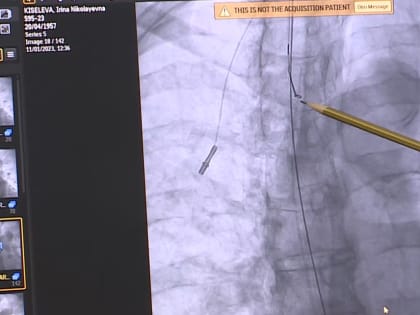

Сосудистые хирурги ООКБ провели орловчанке операцию по удалению отломившейся части порт-системы

Сосудистые хирурги Орловской областной клинической больницы спасли жизнь пациентке, у которой отломился кусок порт-системы и ушел в правое предсердие, сообщает депздрав Орловской области.

В Орле хирурги провели сложную операцию

У орловчанки, которая много лет борется с онкологическим заболеванием, отломилась часть катетера — через него женщина получала химиотерапию, и ушел в предсердие.